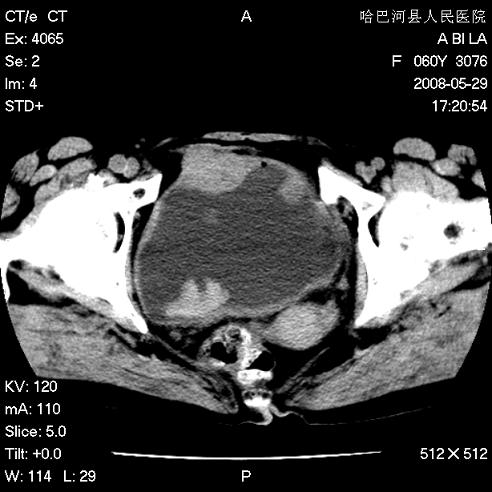

标题: CT13730:排尿不畅4天,抗炎治疗无效,现尿中可见血块 [打印本页]

标题: CT13730:排尿不畅4天,抗炎治疗无效,现尿中可见血块

手术结果及病理:膀胱癌并膀胱壁转移,膀胱内血块